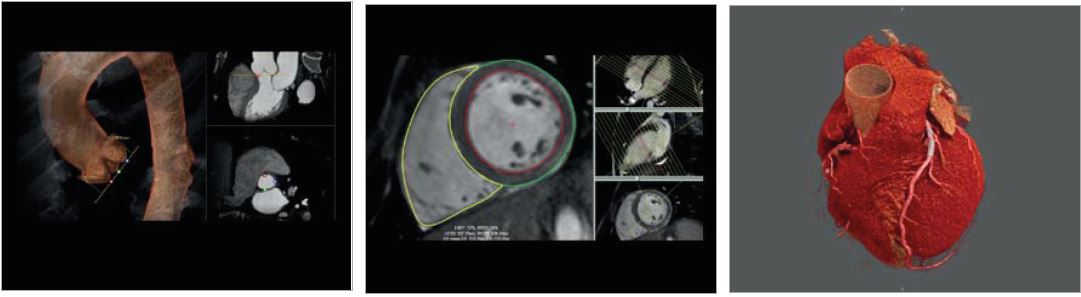

CT Transcatheter Aortic Valve Replacement (TAVR) Planning

Ultra-High Resolution CT

Чітка візуалізація коронарних стентів та детальне окреслення бляшок за допомогою КТ із надвисокою роздільною здатністю. Aquilion Precision — це перший у світі КТ, здатний розпізнавати анатомічні деталі розміром до 150 мікрон, забезпечуючи якість КТ- зображень із роздільною здатністю, яка зазвичай спостерігається лише на ангіографічному обладнанні.

CT Planning

Детальне передпроцедурне планування, включно з додатками, які допоможуть вам під час процедур при структурних захворюваннях серця або ЕФІ інтервенцій.